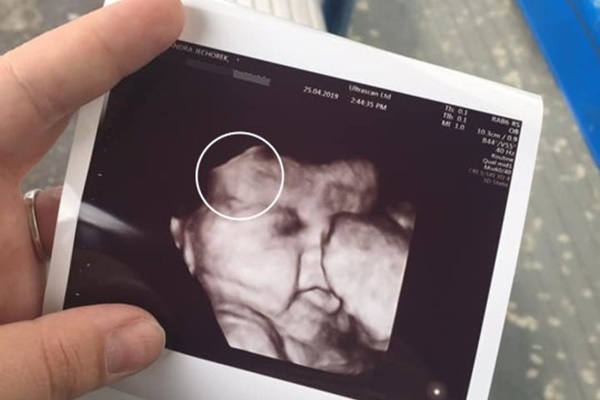

Dây rốn của Maya quá ngắn và xoắn chỉ có thể phát hiện khi siêu âm. Triệu chứng này sẽ hạn chế sự phát triển của thai nhi và tăng tỷ lệ mắc bệnh ở thai nhi.

Dây rốn được coi là ngắn khi nó chưa được 30 cm. Theo số liệu thống kê thì có tới 6% thai nhi có dây rốn quá ngắn. Hiện chưa xác định được nguyên nhân vì sao mà dây rốn lại quá ngắn như vậy nhưng giải thích đơn giản nhất là do thai nhi ít cử động nên dây rốn kém phát triển.

Dây rốn ngắn sẽ không bình chỉnh được ngôi thai hoặc khiến thai nhi khó cử động, nếu dây rốn quá ngắn có thể bị căng quá mức hoặc co thắt lại, làm cắt đứt hoặc giảm sự trao đổi chất giữa mẹ và thai nhi. Thai không nhận được dinh dưỡng và máu nuôi cơ thể sẽ có nguy cơ sinh ra nhẹ cân, thiếu máu. Có những trường hợp cá biệt thai nhi không nhận được oxy từ mẹ nên tử vong trong thai kỳ. Phần lớn các ca có dây rốn ngắn sẽ được chỉ định sinh mổ để đảm bảo an toàn cho cả mẹ và bé.